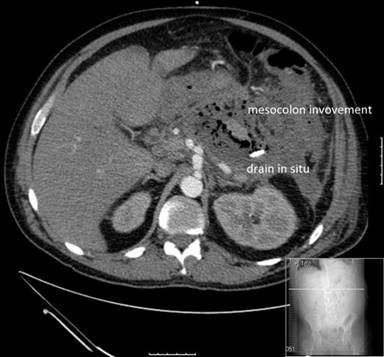

Clinical deterioration merited radiological guided drainage of his peripancreatic collection; fluid from this drain had grown Enterococcus and Escherichia coli sensitive to amoxicillin and potassium clavulanate combination. And while progress was initially satisfactory, his pain worsened and he developed a sepsis syndrome. A repeat CT scan demonstrated on-going fluid collections, almost complete pancreatic necrosis associated with pockets of gas (Figure 1). The patient subsequently had a massive haemorrhage presenting with haematemesis and altered blood in his drain associated with a 3 g/dL drop in his blood haemoglobin. He was urgently transferred to our tertiary pancreatic unit (day 28) for CT angiography which proved to be negative for pseudoaneurysms or on-going haemorrhage. An episode of rectal bleeding 48 hours later prompted a flexible sigmoidoscopy, which showed ischaemic ulceration of the splenic flexure of the colon. A repeat pancreas protocol contrast enhanced CT reported a large heterogeneous collection comprising gas and fluid density in the lesser sac region anterior and continuous with the pancreas. This comprised areas of mixed density interspersed with gas locules. A decision was taken to perform video assisted retroperitoneal pancreatic debridement and abscess drainage to remove the source of local pericolonic irritation. The patient made a slow but good recovery and was subsequently transferred back to the local hospital.

Figure 1. CT scan image showing involvement of mesocolon by pancreatic inflammatory process. |

Several pathogenetic mechanisms have been proposed to explain colonic involvement in acute pancreatitis; direct spread of pancreatic enzymes through the retro-peritoneum to the mesocolon as the cause of pericolitis (Figure 1); thrombosis or compression of one of the mesenteric arteries causes ischaemic necrosis of the colon; and a “low flow state” causing ischaemia of the colon at the junction of the middle and left colic artery blood supply due to hypotension associated with “shock”. Other possible causes for colonic complications are diffuse intravascular coagulation and pressure-necrosis of the colon (e.g., by a surgical drain) [3, 6, 7, 11, 13].